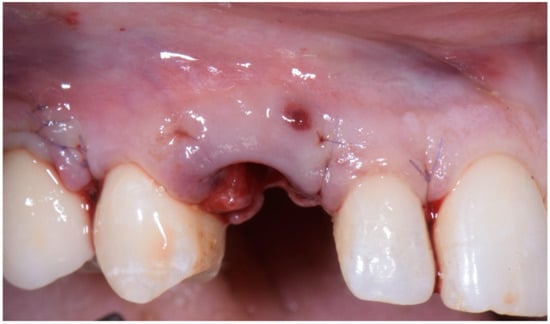

Figure 5. Atraumatic extraction of canine after buccal-flap elevation.